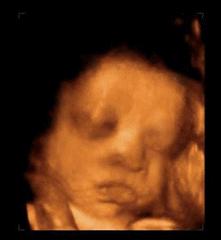

还有,妈妈要是生气了小家伙也能感受到,会跟妈妈一样发脾气。

不过发脾气前要先来一些预备动作:

伸展四肢,抬手活动肩部,准备完毕!

看到小笼包大的拳头没有!我打!

呼!不行,还没解气,我的洪荒之力还没有发泄完,我踢!

所以,妈妈你怀孕的时候千万别生气,一定要天天开心。